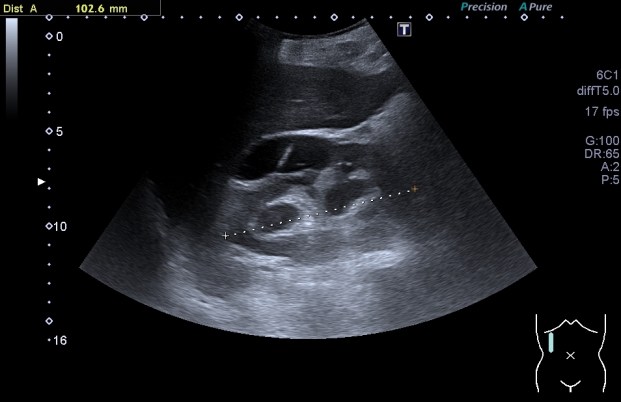

315. Clasificación Bosniak

Vemos con muchísima asiduidad, es sin duda una de las figuras patológicas que más vemos en la exploración del Abdomen, los quistes renales.

Por definición práctica, el quiste renal simple es una estructura ecogénicamente anecoica, de bordes lisos y tersos, que aparecen en un número indeterminado y que constituyen la patología renal más recurrente, estos pueden ser, corticales o parapiélicos

Quiste con septo fino en su interior que en la imagen siguiente comparte espacio con otro septo más grueso que lo clasifica en un nivel superior.

Categoría 2F: Es un quiste simple benigno en un 95% de los casos.

1. Mayor número de septos.

2. Mínimo engrosamiento del septo o calcios groseros o nodulares.

3. Mayores de 3cm.

4. Controles cada 6 meses.

Es desde esta clasificación que en el informe radiológicos se habla del quiste renal como una entidad sospechosa de malignidad.